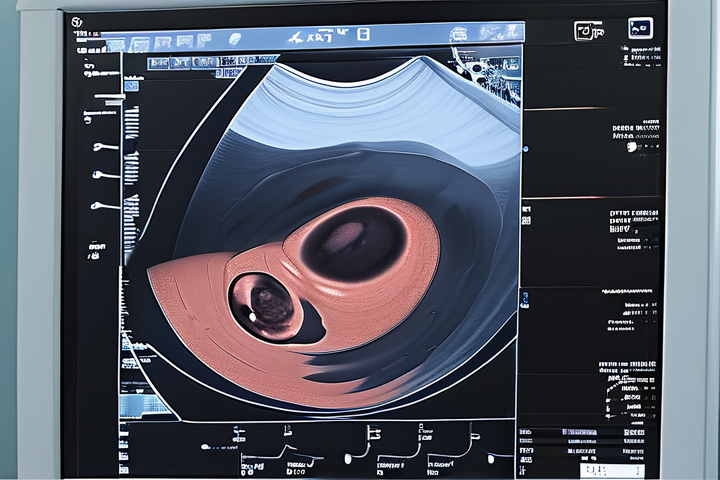

B超检查能够直观地展示胎儿的器官结构和功能发育情况,如心脏、脑部、脊柱等,对于评估胎儿是否正常发育至关重要。

通过B超检查,可以早期发现胎儿畸形、先天性心脏病、羊水过多或过少等问题,及时采取干预措施。

B超检查还可以帮助医生了解子宫大小、胎盘位置、羊水量等指标,对判断妊娠进展和预测分娩方式有重要意义。